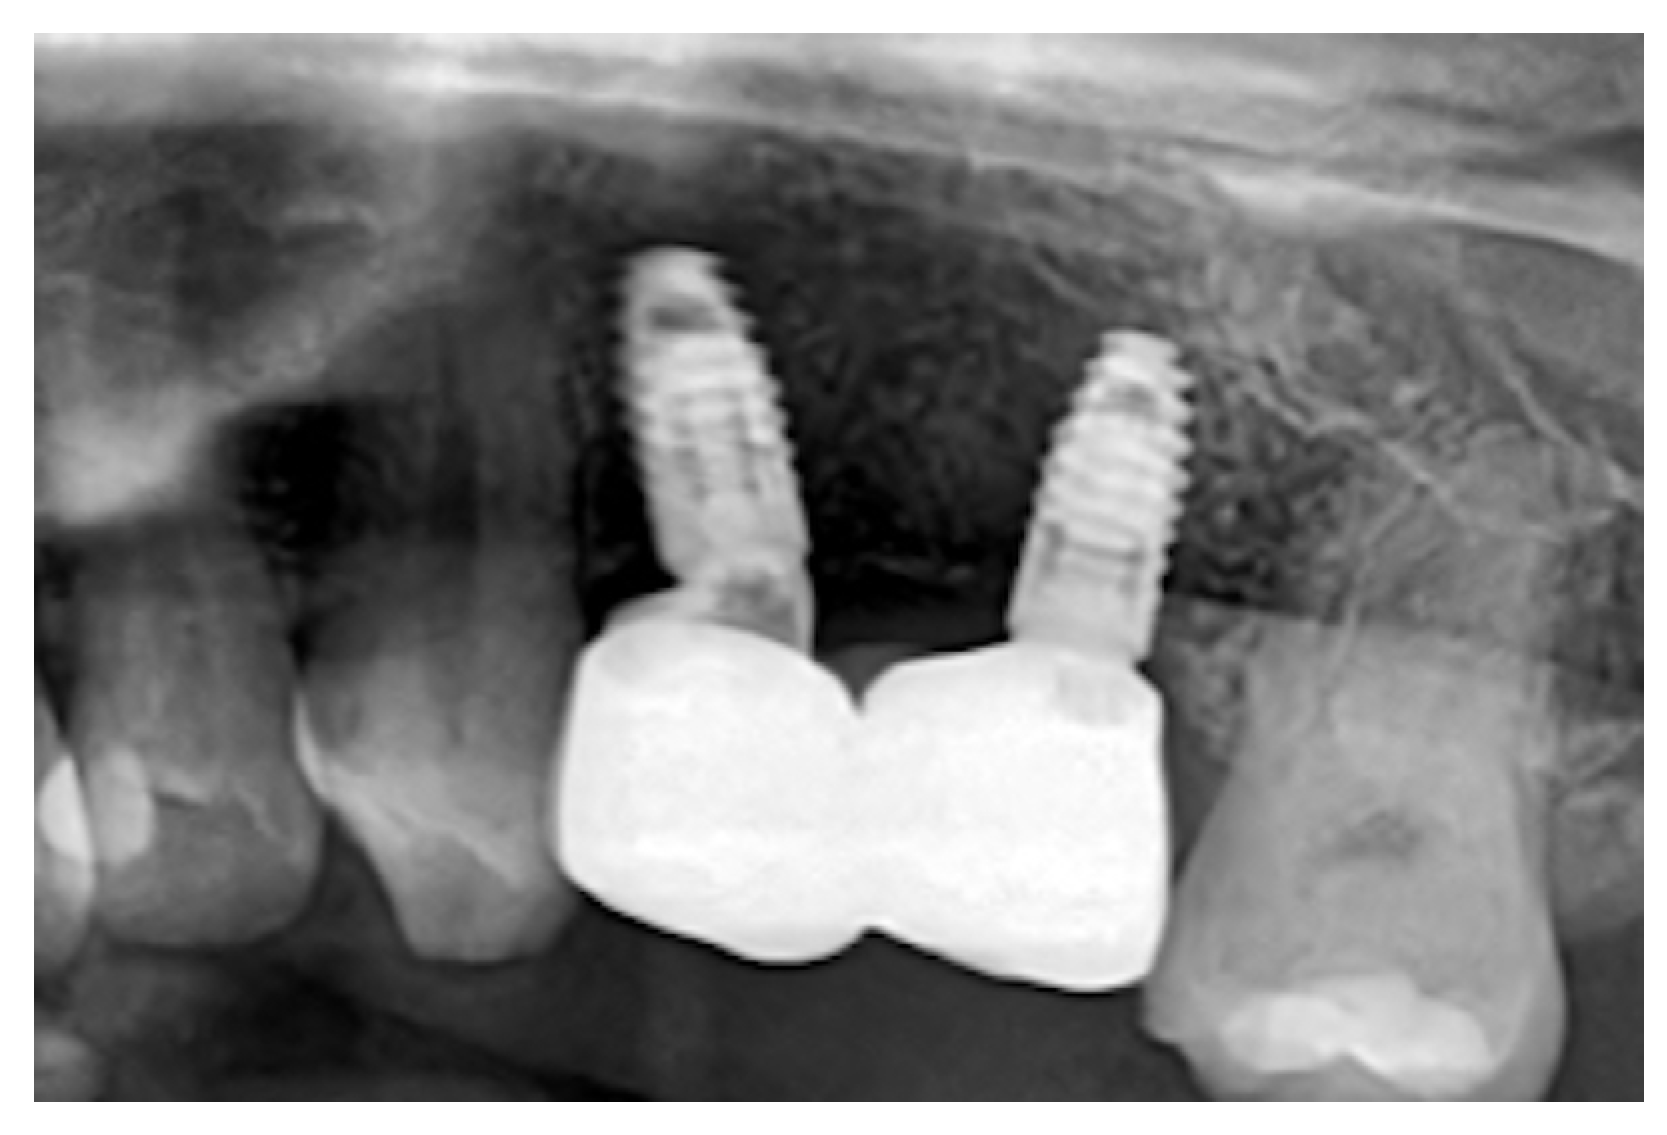

There were no signs of peri-implant inflammation upon follow-up examination and palpation after three years. Additionally, a follow-up X-ray was performed. (Figure 5).

Figure 5. Rx at the 3-year follow-up showing complete bone integration, stable marginal bone levels, and healthy peri-implant tissue contours.